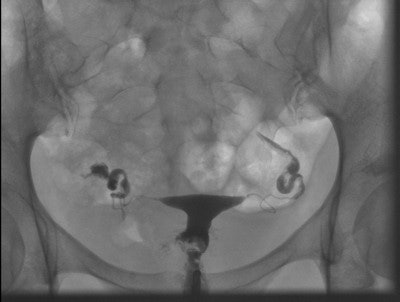

While transvaginal ultrasound is usually the first choice for infertility problems, its usefulness is limited because it cannot assess the morphology and patency of the fallopian tubes -- HSG can. HSG studies have been shown to be important for selecting patients for diagnostic laparoscopy with chromopertubation. Dr. Adrian Schankath from the Institute of Radiology, Kantonsspital Baden, in Baden, Switzerland, and colleagues evaluated all pathologies that were diagnosed by HSG in the workup of female infertility at their institution during a five-year period. They set out to describe the spectrum of diagnostic findings and correlate the diagnostic findings with clinical findings and outcomes.

Patients were identified by searching the institution's RIS for all HSG exams from September 2006 to April 2010. A total of 411 HSG exams were included in their study, with patients ranging in age from 22 to 42 years.

Of all the HSG exams, 226 (55%) were normal, 94 (23%) showed minor abnormalities, and five (1.2%) were not diagnostic. Eighty-six (21%) examinations were pathological. Twenty-nine patients underwent subsequent laparoscopy -- proximal tubal occlusion diagnosed at HSG was ruled out in nine of 23 cases. Follow-up information was unavailable for 20 patients. Nineteen of 66 patients with follow-up after pathological HSG had at least one subsequent successful pregnancy, while 41 patients had no further treatment and no pregnancies.

The detection rate for pathologies using HSG was low (21%) and the false-positive rate was high (39%), the researchers concluded.